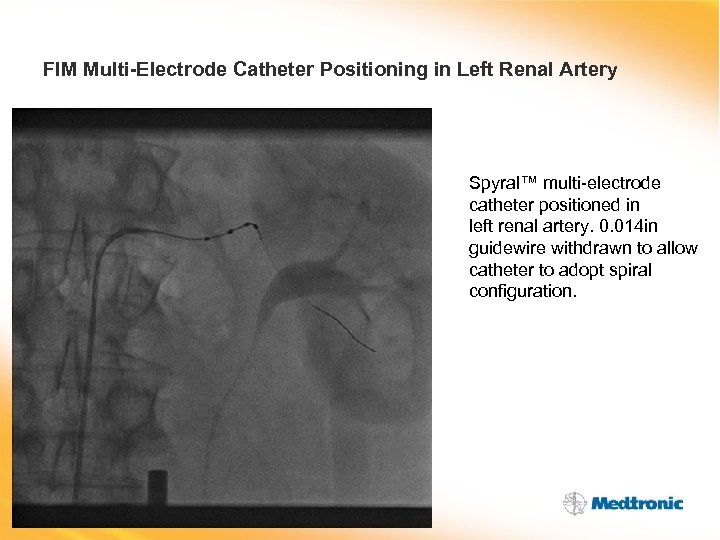

FIM Multi-Electrode Catheter Positioning in Left Renal Artery Spyral™ multi-electrode catheter positioned in left renal artery. 0. 014 in guidewire withdrawn to allow catheter to adopt spiral configuration.

FIM Multi-Electrode Catheter Positioning in Left Renal Artery Spyral™ multi-electrode catheter positioned in left renal artery. 0. 014 in guidewire withdrawn to allow catheter to adopt spiral configuration.